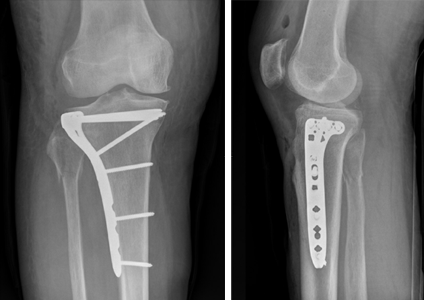

Image

Figure 2: Knee X-rays illustrating a tibial plateau fracture.